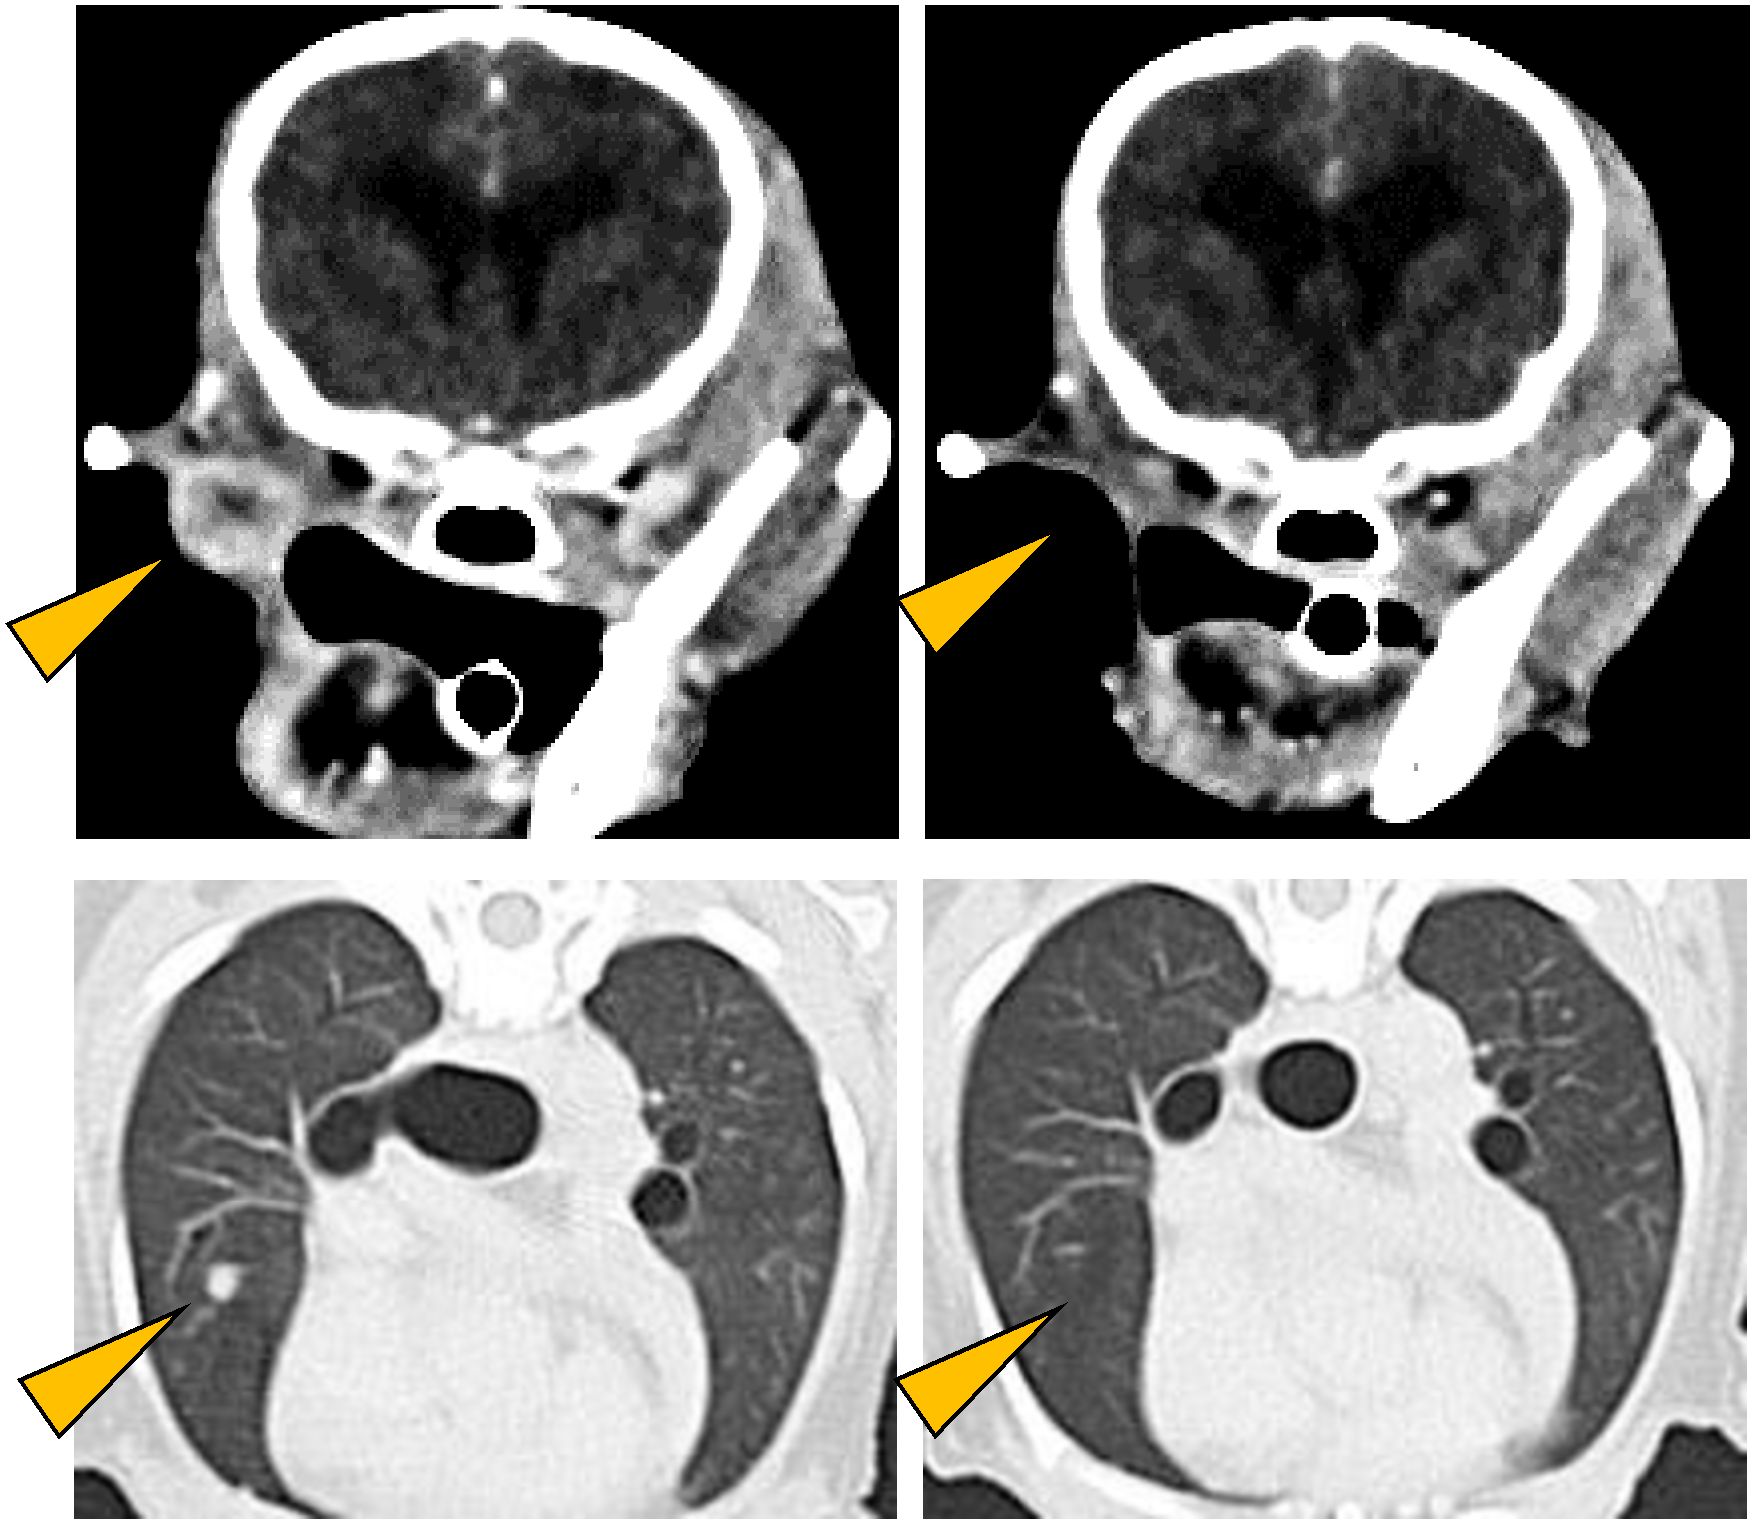

Antitumor effect of anti-PD-L1 antibody.

CT images of oral malignant melanoma (upper left) and its lung metastases (lower left) observed in a Pomeranian (12 years old, male).

As a result of treatment with anti-PD-L1 antibody, all detectable tumors disappeared (right panels) (Maekawa et al. npj Precis. Oncol. 2021).